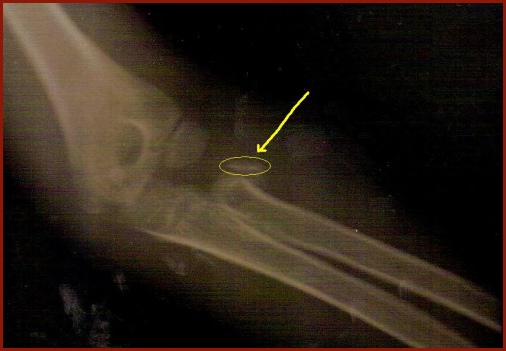

As noted above, Alaina jumped off the tall end of Brushyhenge and landed on her arm, breaking it. Her parents drove her to Children's Hospital in Dallas where they took the above X-ray of her elbow. Notice the small piece of bone that broke off (encircled). To hold that chip in place, a few days later the doctors drove a metal rod into Alaina's wrist that extends all the way to the elbow joint. The rod is inside the bone marrow of her forearm bone. The doctors were able to re-attach the bone frangment using the end of the rod as an anchor point to pin to. In a few weeks they will remove the rod. Wow, that little girl had to go through quite an ordeal! Just one day after the surgery to insert the rod, Alaina was feeling so well that she asked to be taken to school. What a trooper.